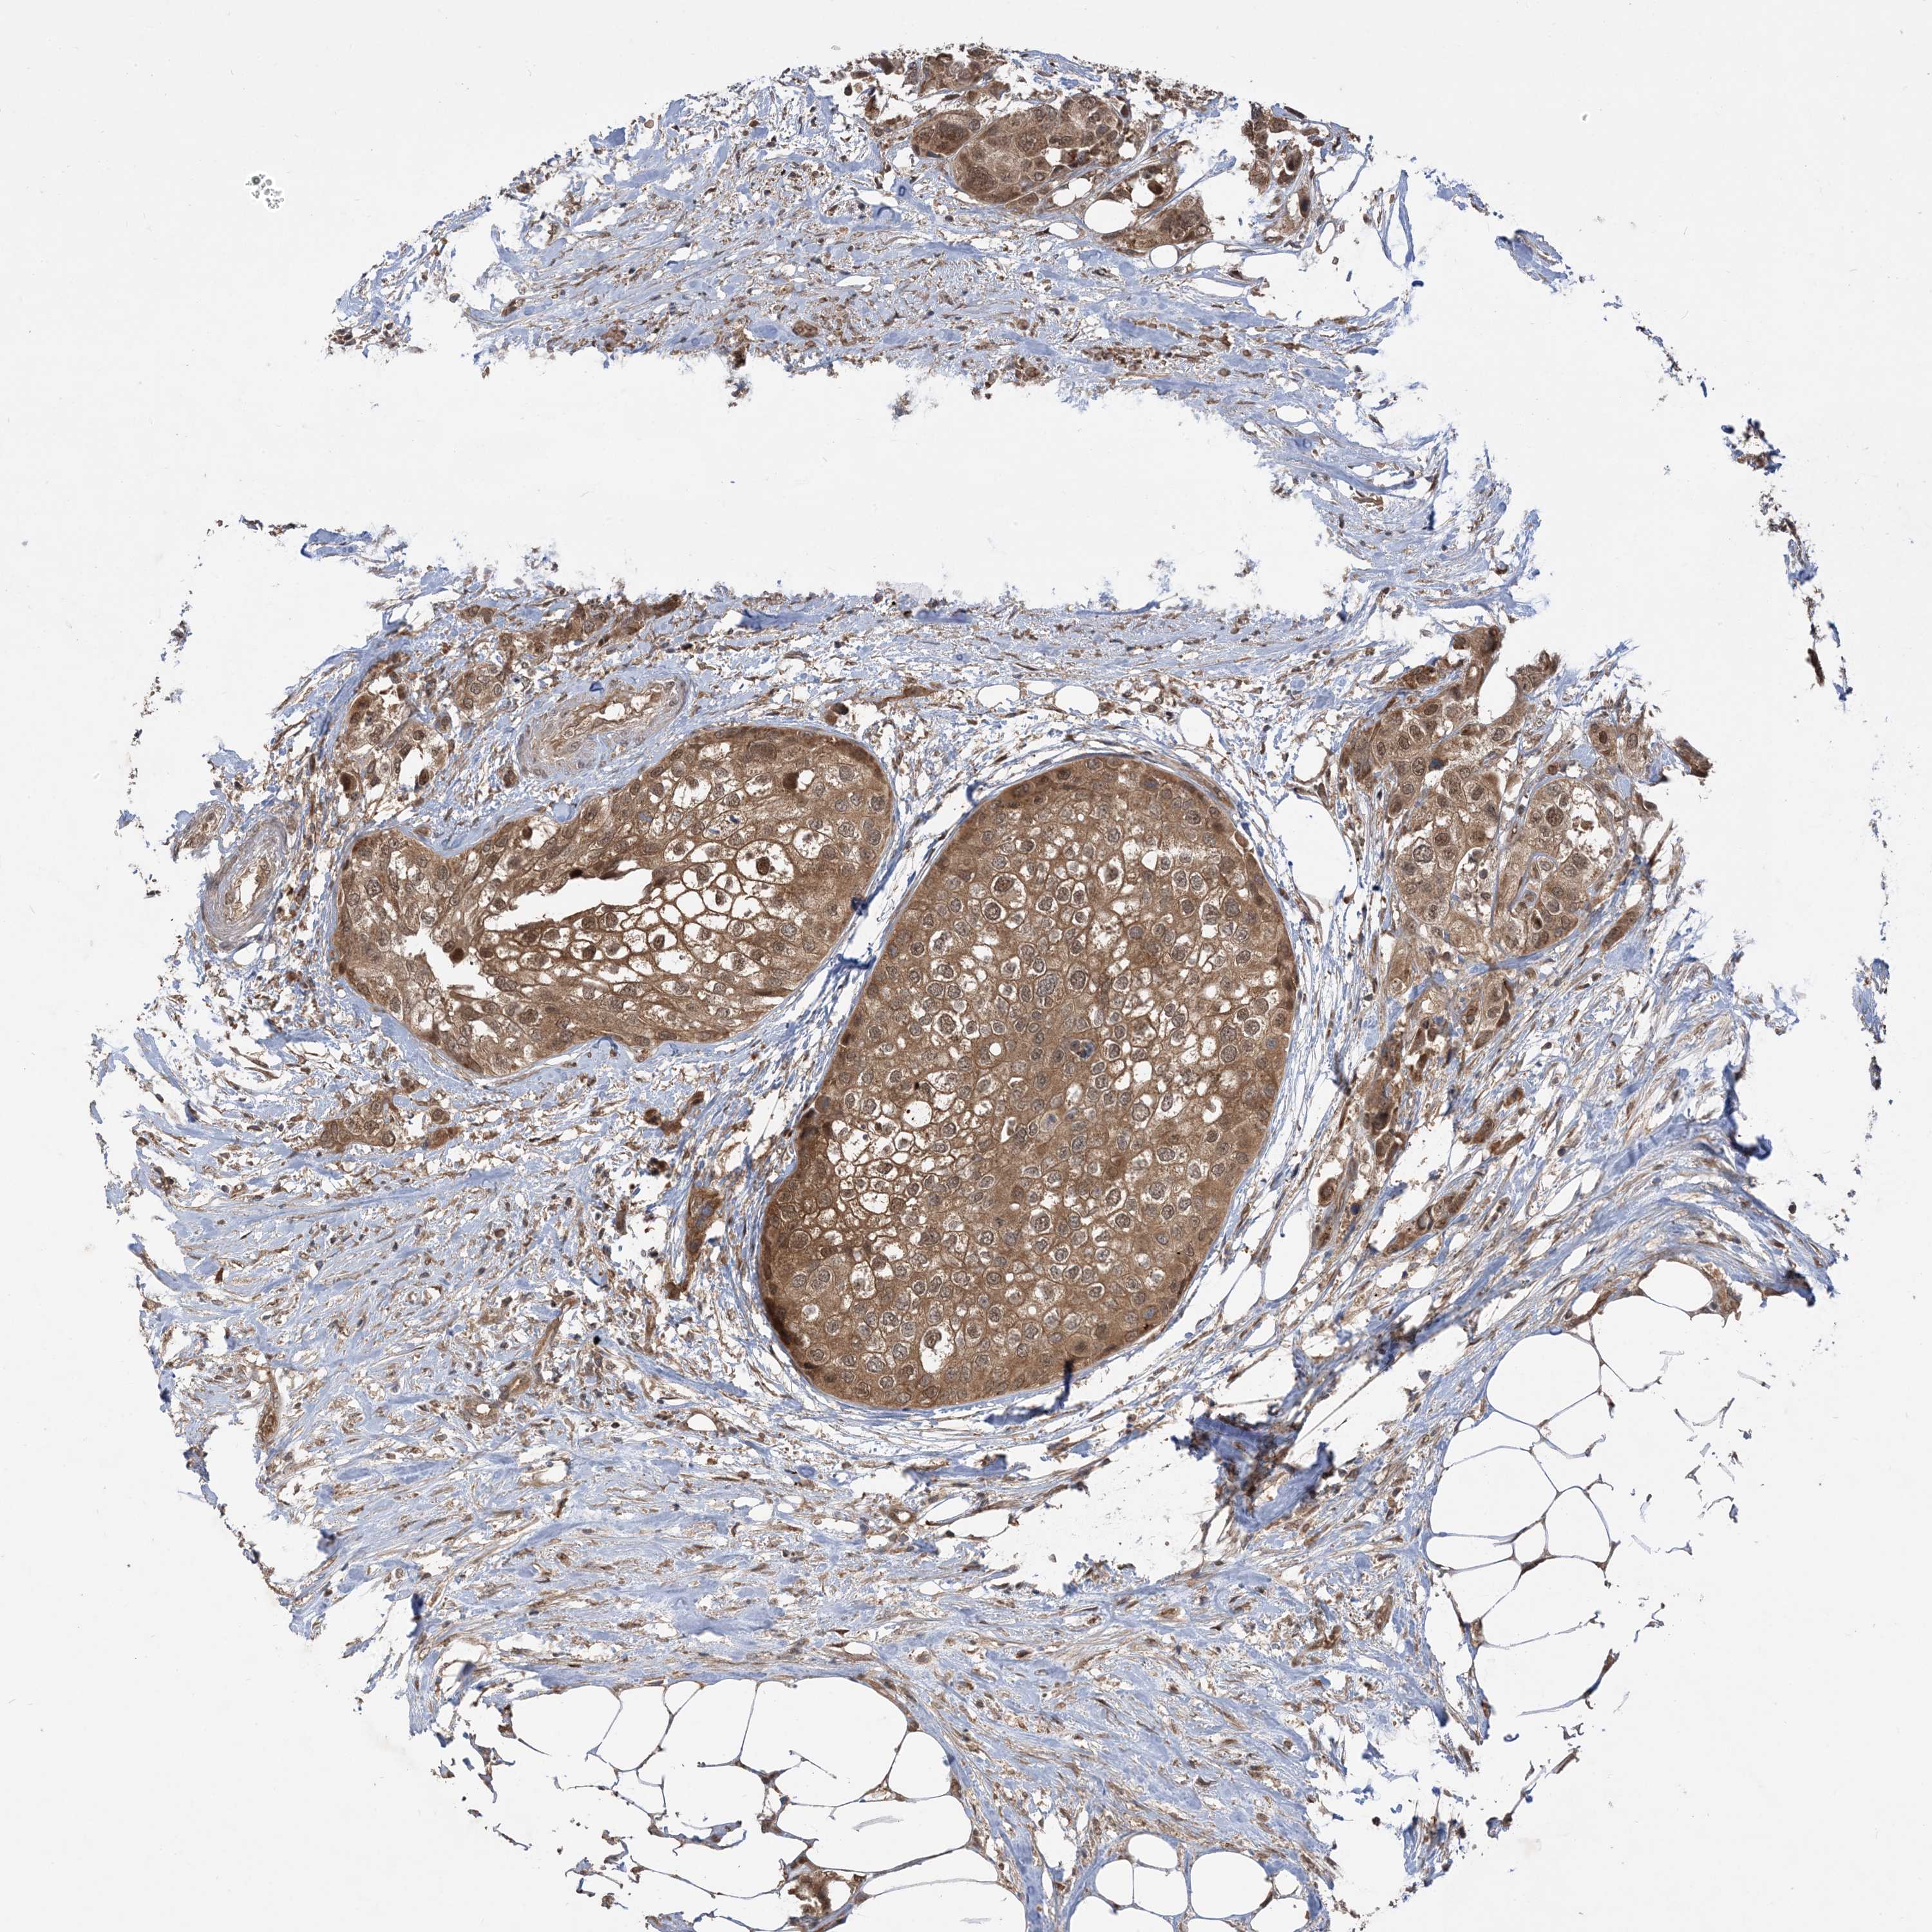

UROTHELIAL CANCER - Protein expressioni

A mouse-over function shows sample information and annotation data. Click on an image to view it in a full screen mode. Samples can be filtered based on level of antibody staining by selecting one or several of the following categories: high, medium, low and not detected. The assay and annotation is described here.

Note that samples used for immunohistochemistry by the Human Protein Atlas do not correspond to samples in the TCGA dataset.

Antibody stainingi

Antibody staining in the annotated cell types in the current human tissue is reported as not detected, low, medium, or high, based on conventional immunohistochemistry profiling in selected tissues. This score is based on the combination of the staining intensity and fraction of stained cells.

Each image is clickable and will lead to virtual microscopy that enables deeper exploration of all samples and also displays staining intensity scores, fraction scores and subcellular localization as well as patient and tissue information for each sample.

Antibody HPA032057

Staining

High

Medium

Low

Not detected

Intensity

Strong

Moderate

Weak

Negative

Quantity

>75%

75%-25%

<25%

None

Location

Nuclear

Cytoplasmic/membranous

Cytoplasmic/membranous,nuclear

Urothelial carcinoma, Low grade

Urothelial carcinoma, High grade